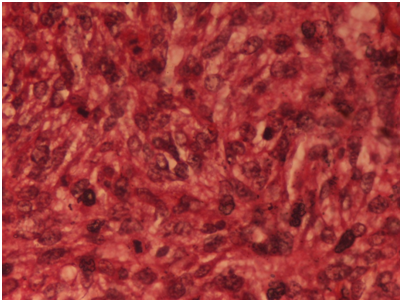

A 22-year-old married female presented in the gynecologic outpatient department with the chief complaints of difficulty in breathing and pain in the lower abdomen since a fortnight. She also complained of fever on and off since 20days with associated weight loss, weakness and fatigue. On physical examination, a mass was felt in the suprapubic region, about 20cm×15cm in size, firm and immobile on palpation. Her laboratory investigations revealed mild microcytic hypochromic anemia and leukocytosis (13,500cells/μl). Liver and kidney functions were normal. Urine analysis revealed no pathology. Pelvic ultrasound and computed tomography revealed a huge and heterogeneous pelvic mass containing solid and cystic areas with ascites measuring 16x13x9cm. Whole body scan revealed no other abnormality. Ascitic tap smear showed only degenerate cells with no viable malignant cells. Chest x-ray revealed left pleural effusion, which on aspiration cytology showed presence of atypical cells suggesting metastatic adenocarcinoma. The serum CA-125 level was markedly raised (126U/ml). Three cycles of neoadjuvant chemotherapy comprising of paclitaxel and carboplatin was administered to relieve her symptoms of breathing, followed by total abdominal hysterectomy with unilateral salpingo-oophorectomy. Laparotomy revealed an unilateral ovarian mass, grossly measuring 13cm×13cm×7cm in size with glistening white and slightly nodular outer surface. Cut surface showed homogenous grayish white solid and cystic areas along with hemorrhage and necrosis (Figure 1). Microscopically section from the tumor showed malignant fascicles of spindle cells with hyperchromatic and pleomorphic nuclei, 30mitosis/10 HPF mixed with areas of necrosis (Figure 2). Necrotic areas might be the carcinomatous component which was responsive to chemotherapy whereas the mesenchymal sarcomatous component was resistant to therapy. Foci of hemorrhage and cystic degeneration were also seen. Histologically, the major part of the tumor consisted of the sarcomatous component which was Van Geison (VG) positive (Figure 3) and showed weak diffuse vimentin positivity on immuno histochemistry (Figure 4). On the basis of clinical findings, gross and microscopic findings, a diagnosis of carcinosarcoma ovary was made.

Figure 3 Histologically, the major part of the tumor consisted of the sarcomatous component which was Van Geison (VG) positive. Van Geisonx40X.